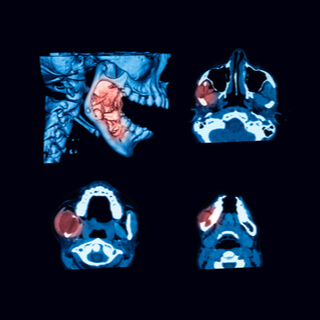

تشخيص سرطان الفك

تتلخّص إجراءات التشخيص فيما يأتي:

• التصوير المقطعي المحوسب.

• الرنين المعناطيسي.

• صورة بانوركس للأشعة السينية.

• الخزعة.